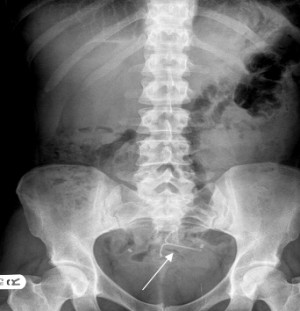

On September 4, 2018, a new product liability lawsuit was filed against Bayer Healthcare by a plaintiff who claims the medical implant Mirena left her with blurry vision and severe headaches. Nichole Thomas, a woman from Tennessee, filed the complaint in the U.S. District Court... Read More